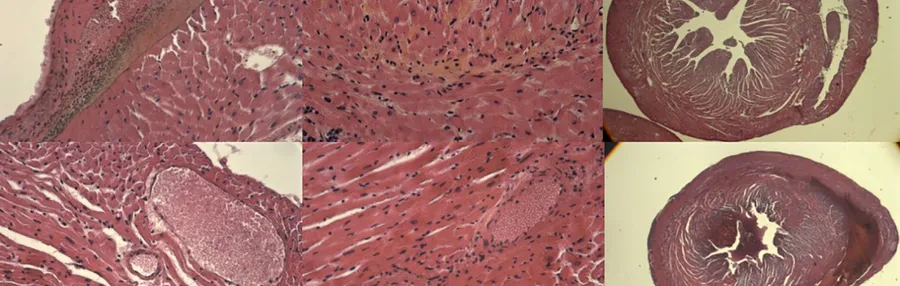

The staff can also carry out animal experiments from tumor grafting to the analysis of results. If necessary, we can also develop specific techniques (e.g. orthotopic grafts, specific tissue toxicity assays) or design specific irradiation set-ups.